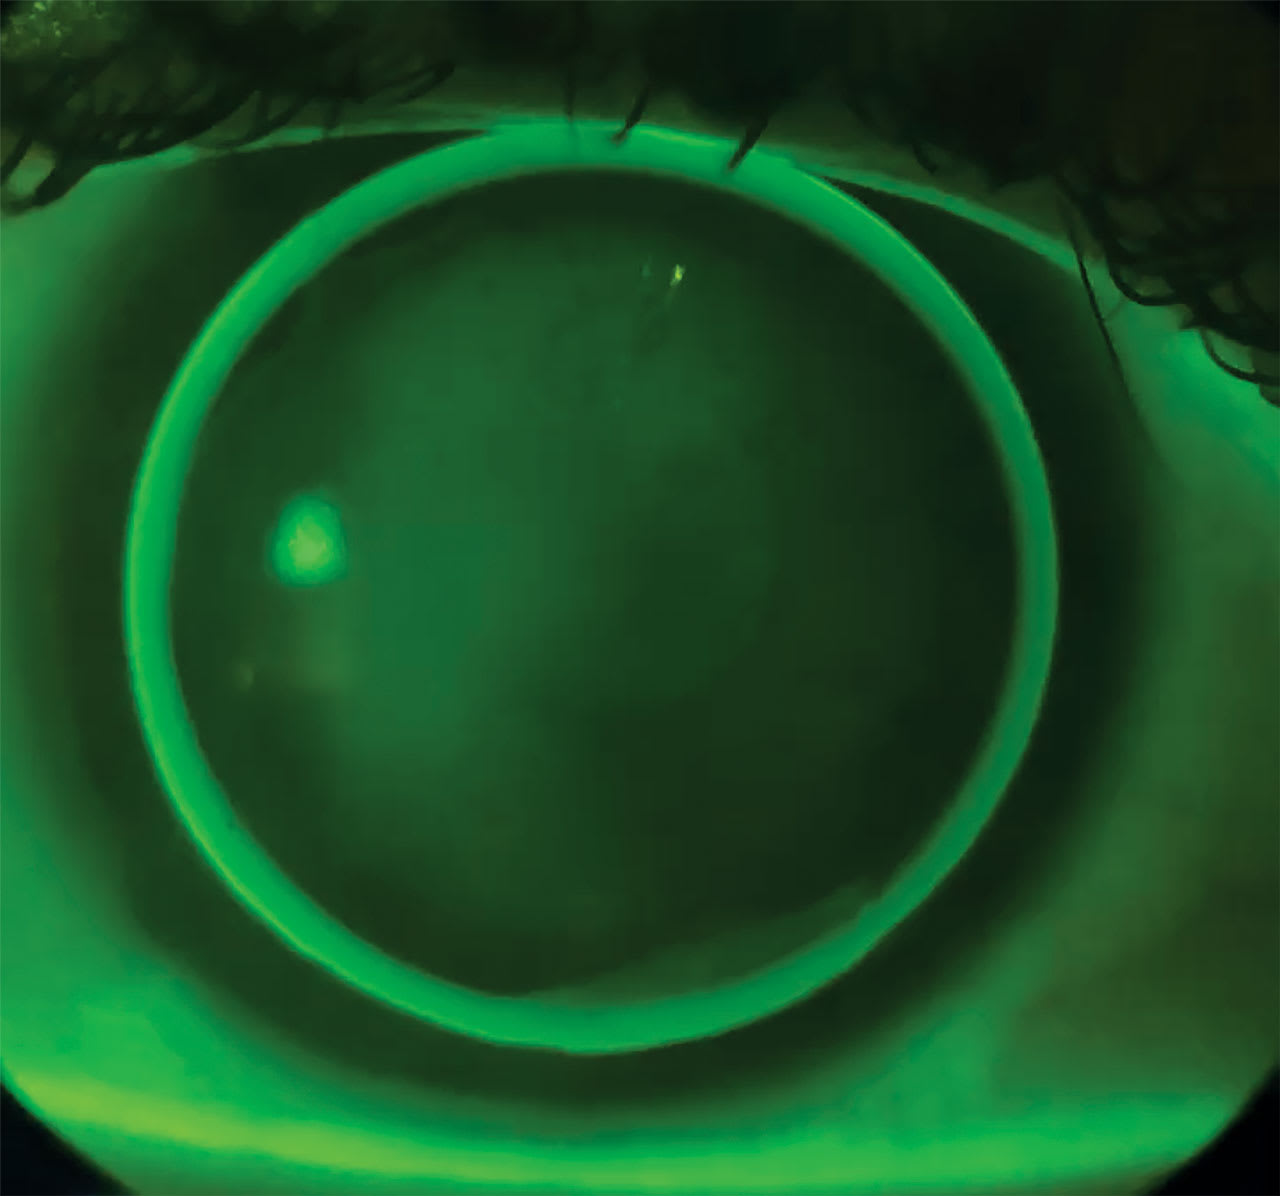

Toric Base Curves: Bitoric and back-surface toric (BST) designs are used for higher amounts of regular corneal astigmatism, typically when the corneal cylinder is above 3.00 DC or the elevation difference is more than about 60 microns (Figure 1). The difference between the 2 designs lies in the optics, with bitoric lenses having cylinder on both sides.